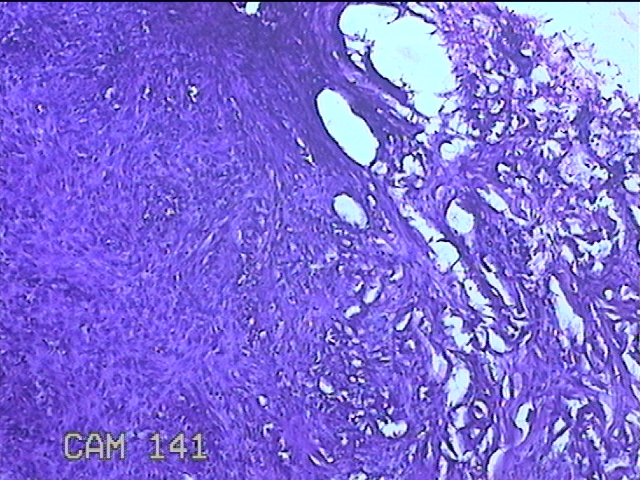

左侧臀部结节

性别

男

年龄

40岁

临床诊断

皮下结节

一般病史

发现左侧臀部结节1年余。

标本名称

大体所见

灰白粉红色组织1.3x0.8x0.3cm一块,表面带梭形皮肤1.3x0.8cm,皮下见结节1.3x1x0.7cm一个,切开结节呈实性,切面灰白粉红色,质软。

图1